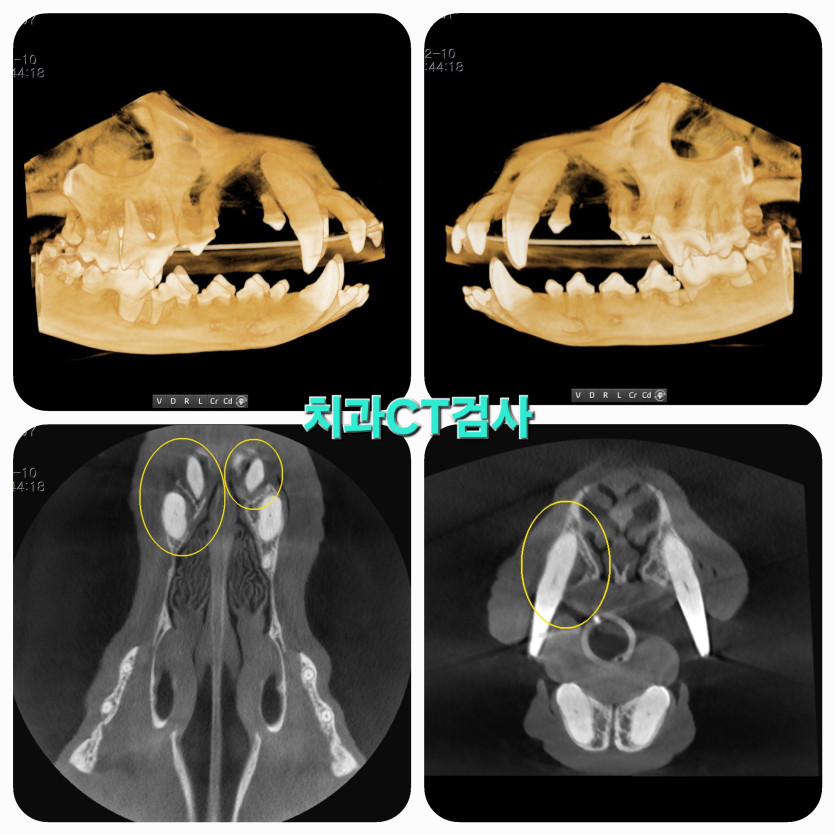

정확한 진단에 강아지를 진심으로 사랑하시는게 마음 깊이 와닿아서 믿고 맡길 수 있었어요.

의사선생님은 초코의 상태를 정확히 진단하시고 아이가 더 이상 아프지 않게 치료해줬어요.